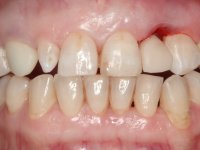

The axis of insertion of the veneer in relation to the abutment was very carefully evaluated. The feldspathic veneers were prepared in the laboratory and then bonded to the mouth after placing absolute insulation. One year later, we began our third phase of treatment, after the veneer in tooth 2.1 fractured. A dental preparation was done on the bonded veneer, seeking to extend the distal inter-proximal interface more to the palate. The objective would be to move the veneer to a more palatine contact point. Preparation of tooth 1.2 was limited to creating an insertion axis. After preparation, the total crown and laboratory veneer were bonded to the mouth. First, the crown was bonded using a relative insulation with Teflon, later the veneer was bonded after the absolute insulation placement. In the crown, I used this type of insulation to avoid the use of staples. It would be difficult to apply due to the shape and size of the tooth, and would also be aggressive to the soft tissues. After bonding procedures, the occlusal integration of the work was evaluated.